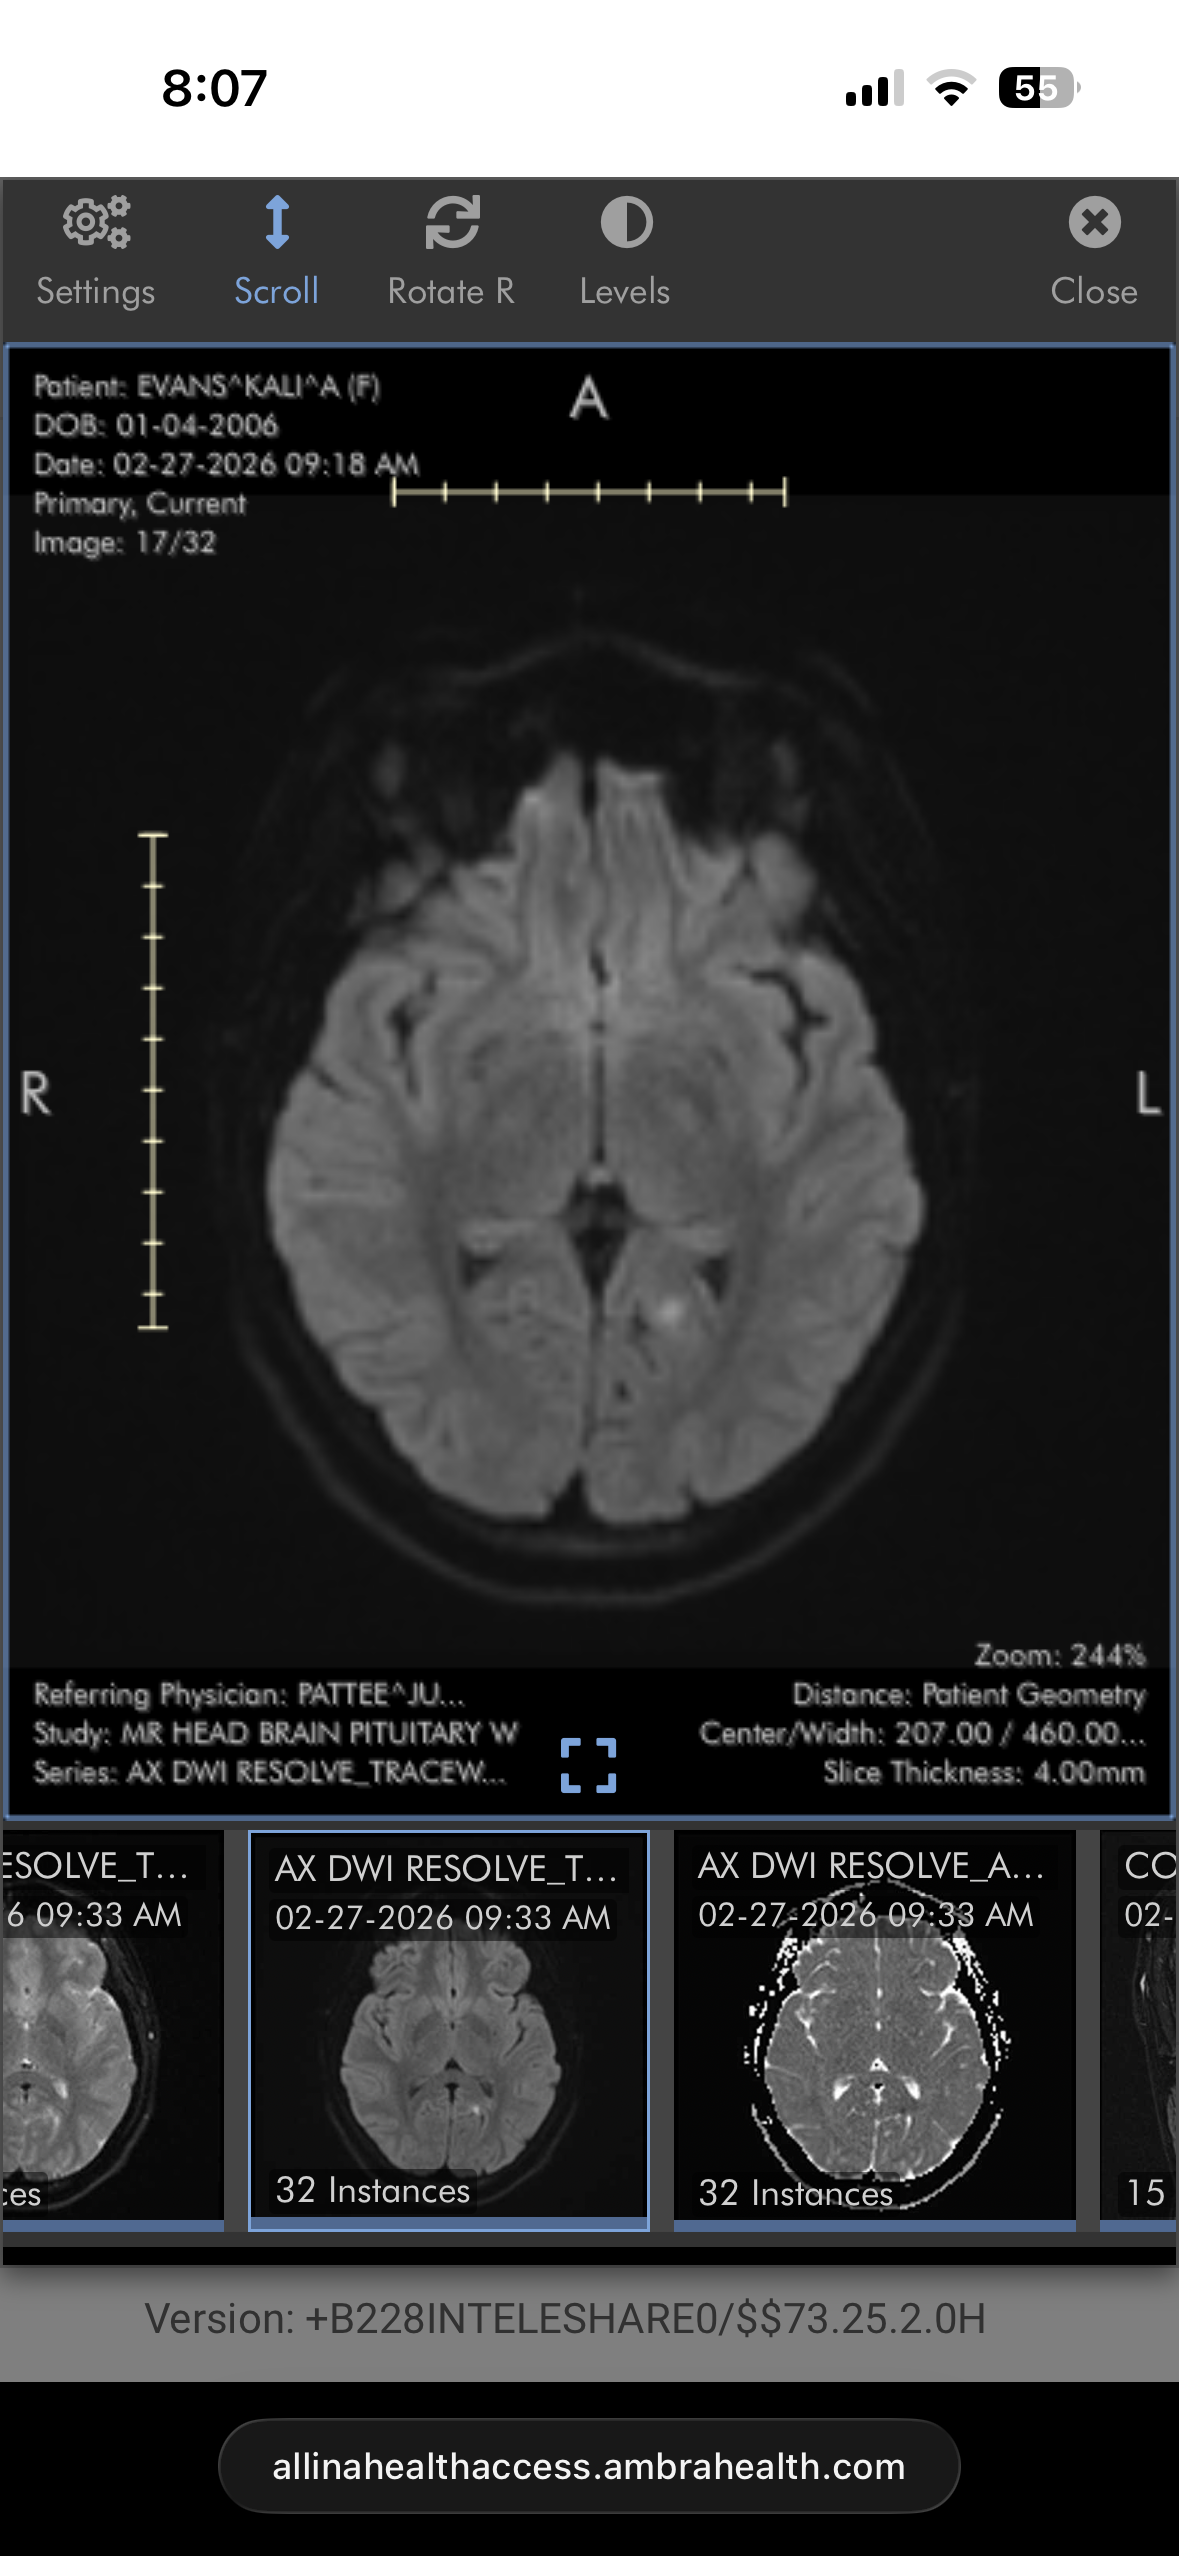

On the evening of February 26th, 2026, Kali suffered two acute ischemic strokes caused by a vessel occlusion in her brain. This was brought on by a previously unknown heart defect called a Patent foramen ovale (PFO). During her pregnancy last year, it was also discovered that she has an enlarged pituitary gland pressing on her optic nerve, causing her to sporadically lose vision. She’s been working with neurology and a hormone specialist since Kai’s birth, but we’re still waiting for more answers. When she lost vision again recently, we thought it was due to the pituitary gland, but it turned out to be strokes. During her hospital stay, the heart defect was found and will need to be repaired. Kali now faces a long recovery with appointments for cardiology, neurology, and occupational therapy. She has lost feeling on her right side, which has delayed her walking and motor skills, and she’s lost peripheral vision, making her unable to drive for now.